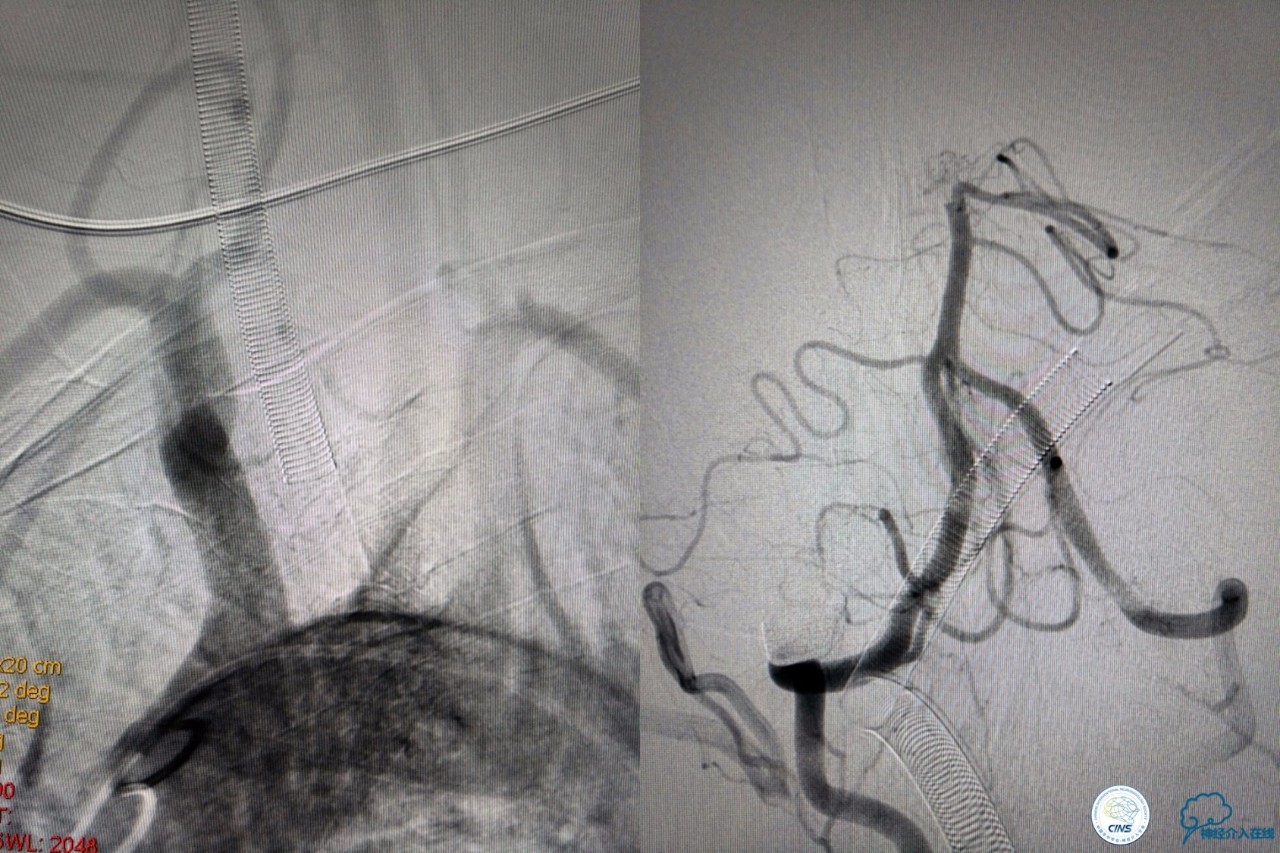

6F导引导管到位至RV2远端,rebar-18微导管及transand微导丝至右侧大脑后动脉P1远端。

solitaireAB4-20mm支架取栓。

基底动脉顶端仍有大量血栓,双侧大脑后动脉未见显影,双侧小脑上动脉再通。再次取栓?还是动脉溶栓?

决定导管内给予替罗非班6ml,复查造影BA顶端仍闭塞,第二次取栓。

第二次取栓后可见基底动脉顶端仍有大量血栓,右侧大脑后动脉开通,但左侧大脑后未见显影且左侧小脑上动脉闭塞!

第三次取栓,支架放入左侧大脑后取栓。

第三次取栓后,左侧大脑后动脉开通,但是栓子再次栓塞右侧大脑后动脉,血栓在基地动脉顶端来回左右摆动,下一次,怎办?血栓负荷太多,可以使用solumbar技术,可以没有颅内导管,没办法,换用更大的支架6-20mm,但费用增加不少,与家属沟通后同意使用,第四次取栓:

血栓负荷还是很大,左侧大脑后再通,但右侧大脑后又闭塞,只能第五次取栓,支架放到右侧大脑后动脉更远。

好大的血栓,支架释放后,血管无复流,拉一把!

没错,没看错!血管成功实现再通,术中取栓的栓子如下。